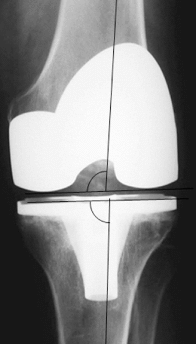

Today, total knee arthroplasty (TKA) is one the most commonly performed surgeries worldwide. The purpose of this article is to review the appearance of normal post-TKA roentgenographs and describe the correct sequence for their interpretation. It is unwise to depend solely on patients' symptoms when diagnosing TKA complications because serial radiographs can foresee failures well before they manifest clinically. Ideal post-TKA radiographs comprise whole lower extremity anteroposterior and lateral views taken under weight bearing conditions along with a skyline view of the patellofemoral joint. Among other things, weight bearing exposes the true alignment, ligamentous laxity and polyethylene wear. On the basis of follow-up of our TKA cases, we have drawn up a protocol for assessing postoperative X-ray films after TKAs. Following the proposed sequence, surgeon can easily decide how to proceed with follow-up and foresee complications. Careful interpretation of postoperative radiographs after TKA is essential to careful monitoring of patients and implant survival.